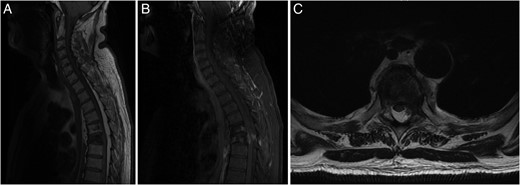

Investigation for his recent ataxia and sensory changes included CT of his thoracic spine (Fig. 1B) and whole spine magnetic resonance imaging (MRI) scan (Fig. 2), which demonstrated marrow infiltrative disease involving the T6 and T5 vertebra, corresponding to the findings seen on previous imaging. The appearance of the T6 fracture compared with CT imaging from 6 months previously had remained largely unchanged. However, there was a significant paravertebral (especially left epidural) disease at T6, likely related to an underlying infiltrative lesion resulting in compression of the thecal sac without spinal cord oedema (Fig. 2). Interestingly, superimposed dorsal epidural lipomatosis was also seen extending along the cervicothoracic spinal canal, from C7 to T10, most severe at the T5 and T6 levels, further contributing to canal stenosis and likely causing the patient's symptoms.

(A) Sagittal T1-weighted MRI showing the T5 and T6 vertebral compression fractures with extensive hyperintense SEL from C7 to T10. (B) Sagittal FAT SAT T1-weighted MRI following gadolinium contrast showing contrast enhancing paravertebral disease mainly at T6 level, with enhancing epidural disease with further canal stenosis from epidural lipomatosis. (C) Axial T2-weighted MRI displaying through T6 level showing compression and right lateral displacement of the thecal sac and spinal cord.